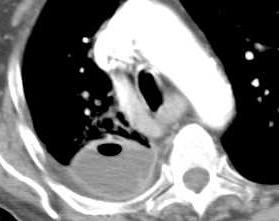

38. EMPIEMA PLEURAL. TEP

Tromboembolismo pulmonar.

Frecuencia del derrame:

Rx: 32%. TC: 47%

Unilateral. 85%

< 1/3 del hemitórax: 90%

Todos exudados

58% con eritrocitos

21% tabicación lo que causa demora en el diagnóstico

TEP. Empiema pleural. Atelectasia redonda

Porcel JM et al. Analysis of pleural effusions in acute pulmonary embolism: radiological and pleural fluid data from 230 patients. Respirology 2007/ Iguchi T et al. Desquamation of the subpleural lung parenchyma caused by empyema after pulmonary embolism: A case report. Respirol Case Rep. 2022 .